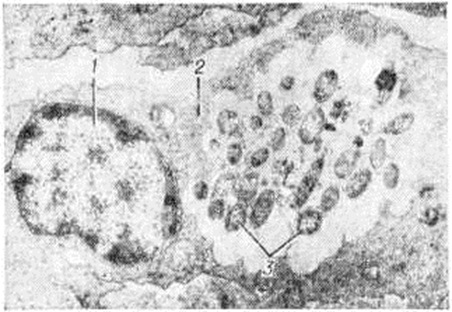

Электронно-микроскопическими исследованиями установлено, что ультраструктура возбудителя Лепра принципиально не отличается от строения других видов грамположительных бактерий. На поверхности микобактерий Лепра выявляется равномерный электроннопроницаемый (осмиофобный) слой толщиной 5—10 нанометров (наружный диффузный слой клеточной стенки). За ним следует осмиофильный слой клеточной стенки толщиной от 3 до 10 нанометров, состоящий из двух очень тонких некоторое, плотно прилегающих друг к другу. Непосредственно к внутренней поверхности клеточной стенки примыкает наружный слой цитоплазматической мембраны (рисунок 1), представляющей собой, как и у других бактерий, трёхслойную мембрану толщиной 7,5—9 нанометров. В бактериальной клетке встречаются 1—2 мезосомы с выраженным полиморфизмом (петлеобразные, везикулярные, трубчатые, пластинчатые, гроздевидные). В цитоплазме выявляется сравнительно небольшое количество рибосом, сферические электронно-плотные включения волютина диаметром 20—50 нанометров, включения, имеющие вид ограниченных мембраной вакуолей (предположительно липоиды), и гомогенные тельца, природа которых остаётся неизвестной. Ядро не имеет определённой формы, расположено в центре клетки вдоль её длинной оси, не ограничено мембраной. Иногда в лизирующихся под воздействием химиотерапии клетках микобактерий Лепра выявляются спороподобные образования (рисунок 2 и 3).

Рис. 3. | ||

Основным способом размножения микобактерий Лепра является деление материнской клетки и врастания поперечной перегородки. Микобактерия Лепра является облигатным внутриклеточным паразитом тканевых макрофагов или клеток ретикулоэндотелиальной системы, проявляет выраженный тропизм к коже и периферическим нервам, но на поздних стадиях развития процесса встречается также во многих других клетках и тканях организма. В тканевой клетке микобактерии Лепра размножаются только в цитоплазме (рисунок 4); внутриядерный паразитизм для них нехарактерен. Микобактерии в лепрозных клетках иногда отграничены от цитоплазмы клетки-хозяина фагосомной мембраной. На поздних стадиях инфекции паразитирование возбудителей Лепра человека сопровождается нарушением строения эндоплазматического ретикулума и митохондрий клетки-хозяина.